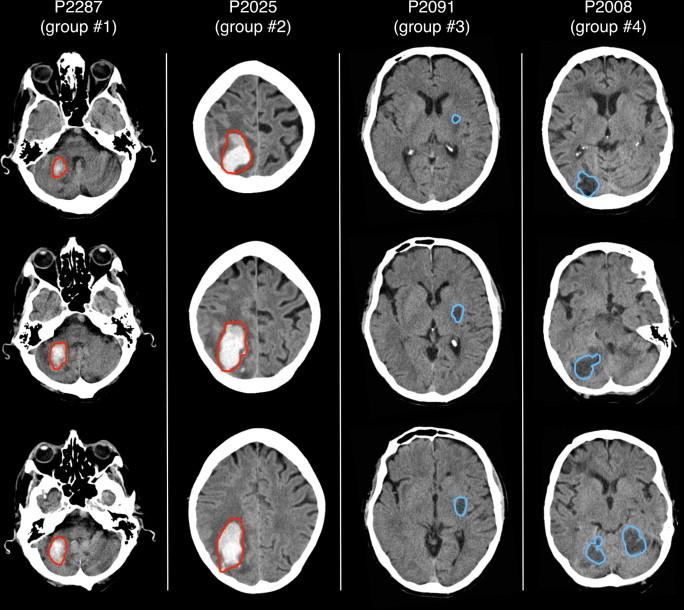

利用脑部CT图像自动勾勒中风病灶

Automated delineation of stroke lesions using brain CT images.

Computed tomographic (CT) images are widely used for the identification of abnormal brain tissue following infarct and hemorrhage in stroke. Manual lesion delineation is currently the standard approach, but is both time-consuming and operator-dependent. To address these issues, we present a method that can automatically delineate infarct and hemorrhage in stroke CT images. The key elements of this method are the accurate normalization of CT images from stroke patients into template space and the subsequent voxelwise comparison with a group of control CT images for defining areas with hypo- or hyper-intense signals. Our validation, using simulated and actual lesions, shows that our approach is effective in reconstructing lesions resulting from both infarct and hemorrhage and yields lesion maps spatially consistent with those produced manually by expert operators. A limitation is that, relative to manual delineation, there is reduced sensitivity of the automated method in regions close to the ventricles and the brain contours. However, the automated method presents a number of benefits in terms of offering significant time savings and the elimination of the inter-operator differences inherent to manual tracing approaches. These factors are relevant for the creation of large-scale lesion databases for neuropsychological research. The automated delineation of stroke lesions from CT scans may also enable longitudinal studies to quantify changes in damaged tissue in an objective and reproducible manner.

摘要

计算机断层扫描(CT)图像被广泛用于识别中风后梗死和出血导致的异常脑组织。目前手动勾勒病变是标准方法,但既耗时又依赖操作人员。为了解决这些问题,我们提出了一种能够自动勾勒中风CT图像中梗死和出血区域的方法。该方法的关键要素是将中风患者的CT图像准确归一化到模板空间,并随后与一组对照CT图像进行逐体素比较,以确定信号强度减低或增高的区域。我们使用模拟病变和实际病变进行的验证表明,我们的方法在重建梗死和出血导致的病变方面是有效的,并且生成的病变图在空间上与专家操作人员手动生成的病变图一致。一个局限性是,相对于手动勾勒,自动方法在靠近脑室和脑轮廓的区域灵敏度降低。然而,自动方法在节省大量时间以及消除手动追踪方法固有的操作人员间差异方面具有诸多优势。这些因素对于创建用于神经心理学研究的大规模病变数据库具有重要意义。从CT扫描中自动勾勒中风病变还可能使纵向研究能够以客观且可重复的方式量化受损组织的变化。